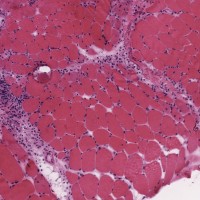

Inclusion body myositis (IBM)

A male-predominant slowly progressive idiopathic inflammatory condition of patients over the age of 50.

Clinical features include asymmetric weakness of the finger flexors and the quadriceps muscles.